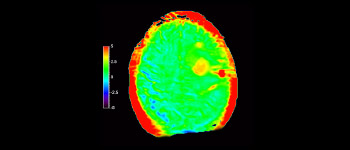

Neurologische Leiden stellen eine schwere Belastung dar. Philips hat es sich zum Ziel gesetzt, hochwertigste Neuro-Bildgebung zu ermöglichen – für eindeutige Diagnosen und eine schnelle Therapie. Wenngleich die MRT heutzutage den Goldstandard in der neuroradiologischen onkologischen Bildgebung darstellt, kann die Genauigkeit beim Tumor-Grading und den Nachsorgeuntersuchungen noch weiter verbessert werden. 3D APT (Amide Proton Transfer) ist eine einzigartige, kontrastmittelfreie Methode zur MR-Tomographie des Gehirns, die den Bedarf nach einer sichereren Diagnose in der Neuroonkologie erfüllt. 3D APT nutzt das Vorhandensein von endogenen zellulären Proteinen zur Erzeugung eines MR-Signals, das direkt mit der Zellproliferation, einem Marker für Tumoraktivität, korreliert. 3D APT kann geschulte medizinische Fachkräfte dabei unterstützen, gering differenzierte von hochdifferenzierten Gliomen und Tumorverhalten von Behandlungseffekt zu unterscheiden1.

APT wurde bei etwa 70 MR-Untersuchungen von Kindern mit Hirntumor eingesetzt, und wir haben einige ermutigende Erstergebnisse.“

John Curran, MD

Radiologe am Phoenix Children’s Hospital (PCH)